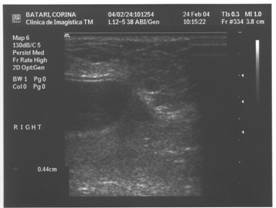

Ecografia este usor de realizat. Ecografic se pot decela:

- ruptura implantului; formatiuni nodulare anecogene in tesutul mamar periprotetic nedepresibile de presiune ( spre deosebire de colectiile lichidiene periprotetice );

- ecografia identifica doar colectiile de dimensiuni mari. Ea pune diagnosticul in epansamentele precoce, hematom, limfocel sau serozitate inflamatorie ( colectie transsonica periprotetica deformabila );

- ecografia este, in fine, utila in diagnosticul mastopatiilor benigne sau maligne. Ea va putea, eventual, preciza natura unei opacitati de pe mamografie;

- ecografia nu va evidentia microcalcificarile.